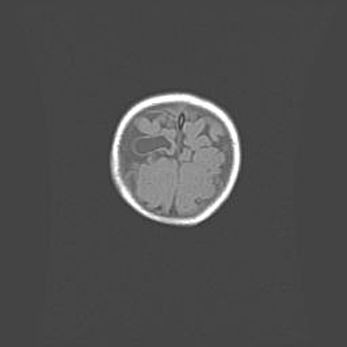

Открытая гидроцефалия.

Возраст: 9 месяцев 12 дней

Вес: 6800 г

Пол: мужской

Окружность головы: 41,5 см

Срок гестации: 28 недель

Гидроцефалия головного мозга у новорожденных имеет характерный признак: опережающий рост окружности головы приводит к визуально хорошо определяемой гидроцефальной форме сильно увеличенного в объёме черепа. Детские неврологи определяют следующие симптомы гидроцефалии у грудничков: выбухающий напряжённый родничок, частое запрокидывание головы, смещение глазных яблок к низу.